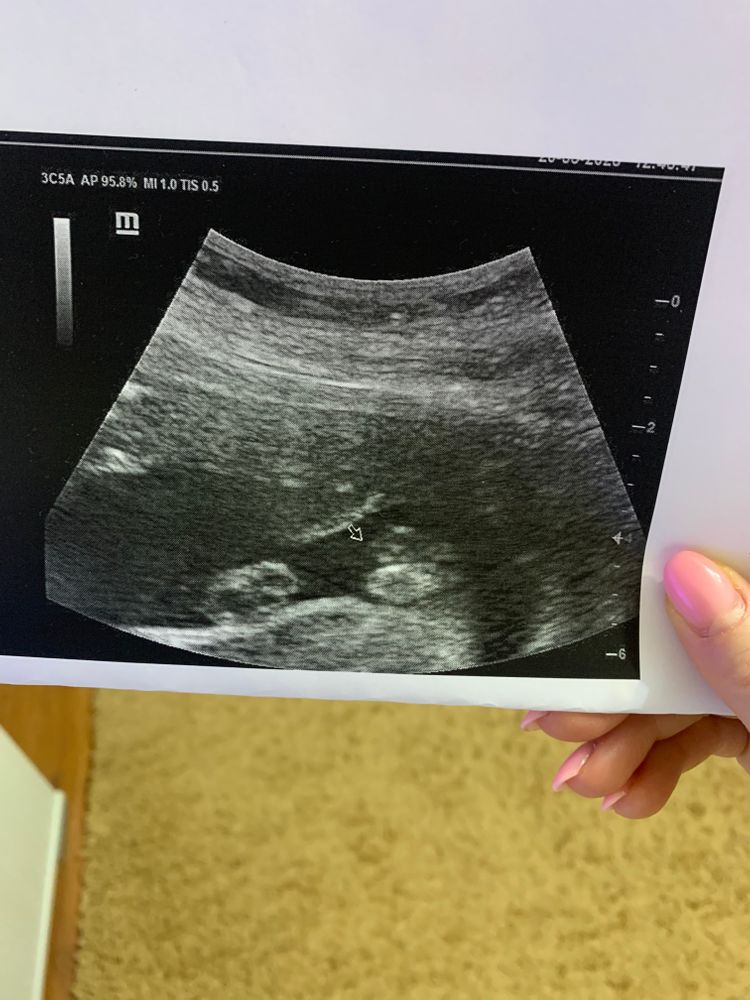

Мальчик или девочка?

На раннем сроке различия между девочкой и мальчиком небольшие, поэтому могут перепутать. Потом уже яснее. Здесь на девочку похоже.

На 13 неделе определение пола в большей степени угалайка, 50 на 50 😁

Виортэя, самое интересное что мы и не спрашивали, 13 недель, рано. Узист сам сказал. Нам все равно с самого начала было кто там, любим одинаково. А вот когда началась эта путанница думаю надо еще на доп узи. Спасибо за совет на счет скидок, посмотрю обязательно. С так 5000 примерно этот анализ стоит